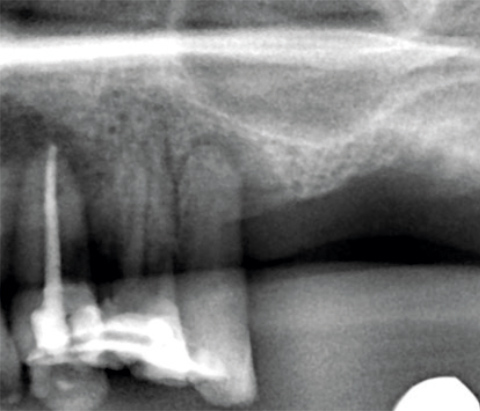

Komplexe laterale und

vertikale Rekonstruktion in

der ästhetischen Zone

Dr. Frederic Kauffmann

Deutschland